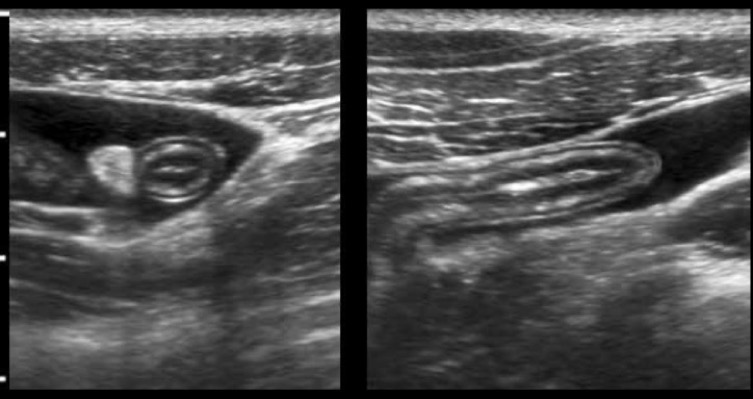

Intestin normal en US

Rappel: - ACCOLEMENT DES MUQ Ligne hyper-US

- MUQ hypo-US

- SS-MUQ hyper-US

- MUSC hypo-US

- SEREUSE Ligne hyper-US

JEJUNUM NORMAL

ILEON NORMAL